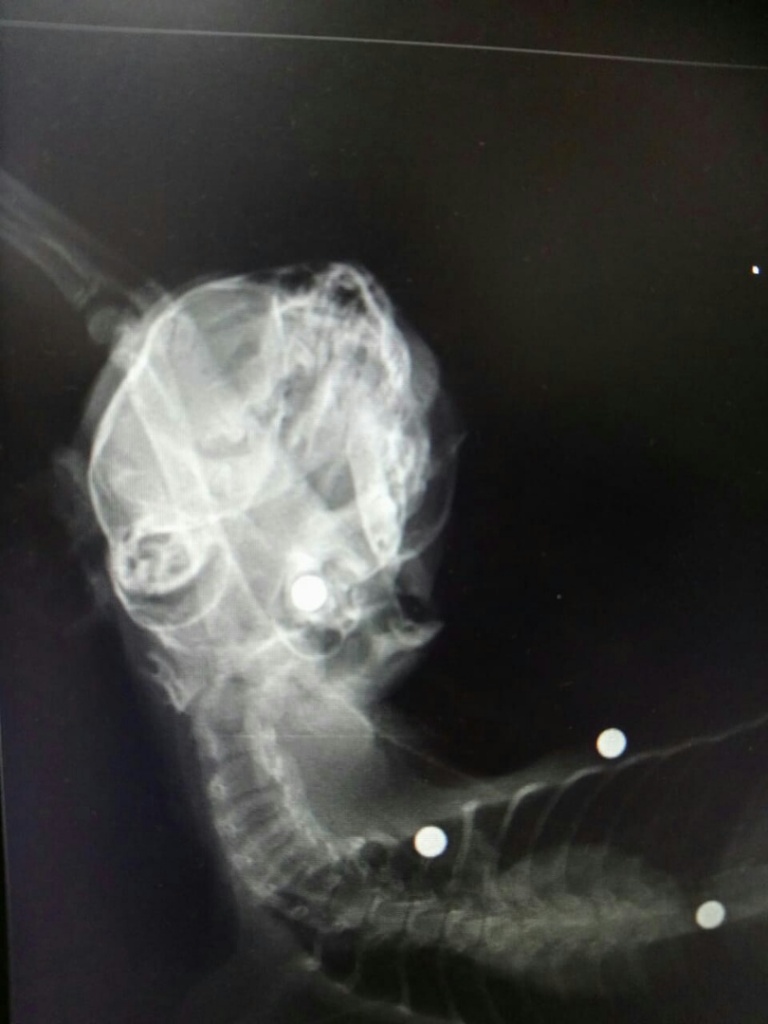

Котенок медленно умирал, жалобно мяукая. Было очевидно, что котенку очень больно. Чтобы понять, что доставляет маленькой кошечке такую невыносимую боль, небезразличная женщина отнесла ее в ближайшую ветеринарную клинику. Обследование и рентген показали, что тело малыша буквально изрешечено пулями — они были в районе многих внутренних органов и даже в глазах. Всего ветеринары насчитали 8 пуль. В ближайшие дни котейке предстоит операция по извлечению инородных предметов, ее подлечат и попытаются пристроить в добрые руки.

фото: vk.com БГ ОО ЗЖ "Доброе сердце"